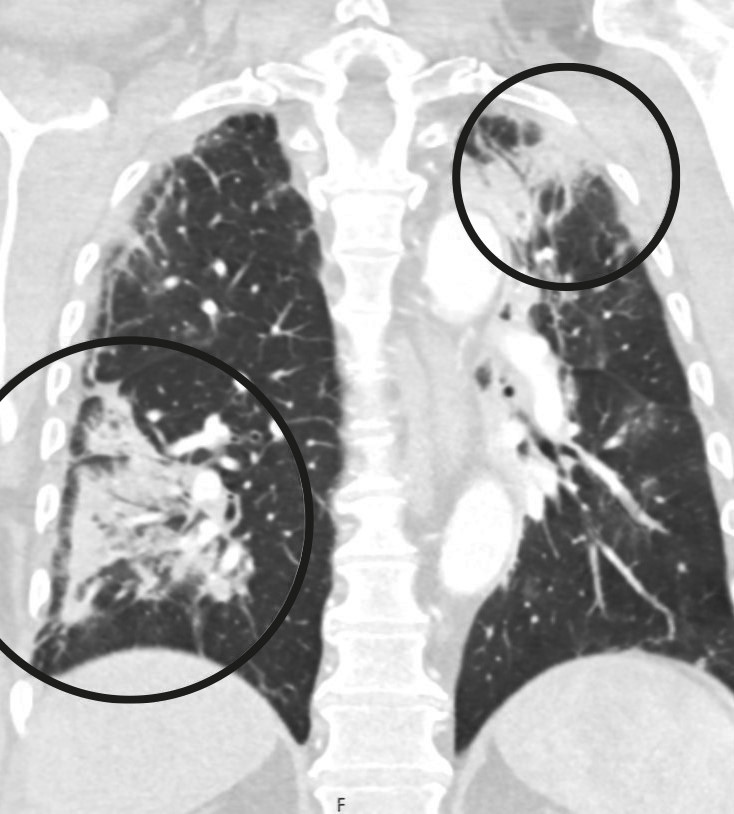

A PCR test on admission was negative for COVID-19 and the patient had no respiratory symptoms. CT angiography showed a filling defect from both popliteal arteries in the knee joint (Figure 1). He also had occlusions distally with localised refilling in the calf arteries, consistent with thrombosis in both lower extremities. The patient was given 5 000 IU dalteparin before being transferred to a regional hospital.

Upon arrival at the regional hospital, the patient had stable respiration and circulation. His lower left extremity was showing signs of acute ischaemia, with pain and reduced sensation, but preserved motor function. The symptoms in his lower right extremity had gradually improved over the course of the day, and the patient now had normal sensation and motor function, but continuing peripheral coldness. An acute bilateral mechanical thromboembolectomy of the popliteal artery and tibiofibular trunk was performed under general anaesthesia. Good circulation was achieved in both lower limbs postoperatively.